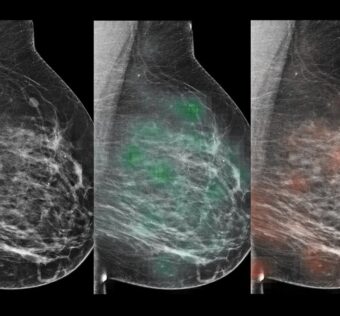

![]() Artificial Intelligence Can Predict Long-Term Risk of Invasive Breast Cancer

DistilINFO Hospital IT - (Tuesday May 30, 2023) Cutting-edge research from Mayo Clinic and UCSF demonstrates that combining artificial intelligence (AI) imaging with volumetric breast density algorithms can accurately predict the long-term risk of invasive breast cancers. The study compared traditional assessment… ![]() Patients Know Best announces 6B as new tech partner